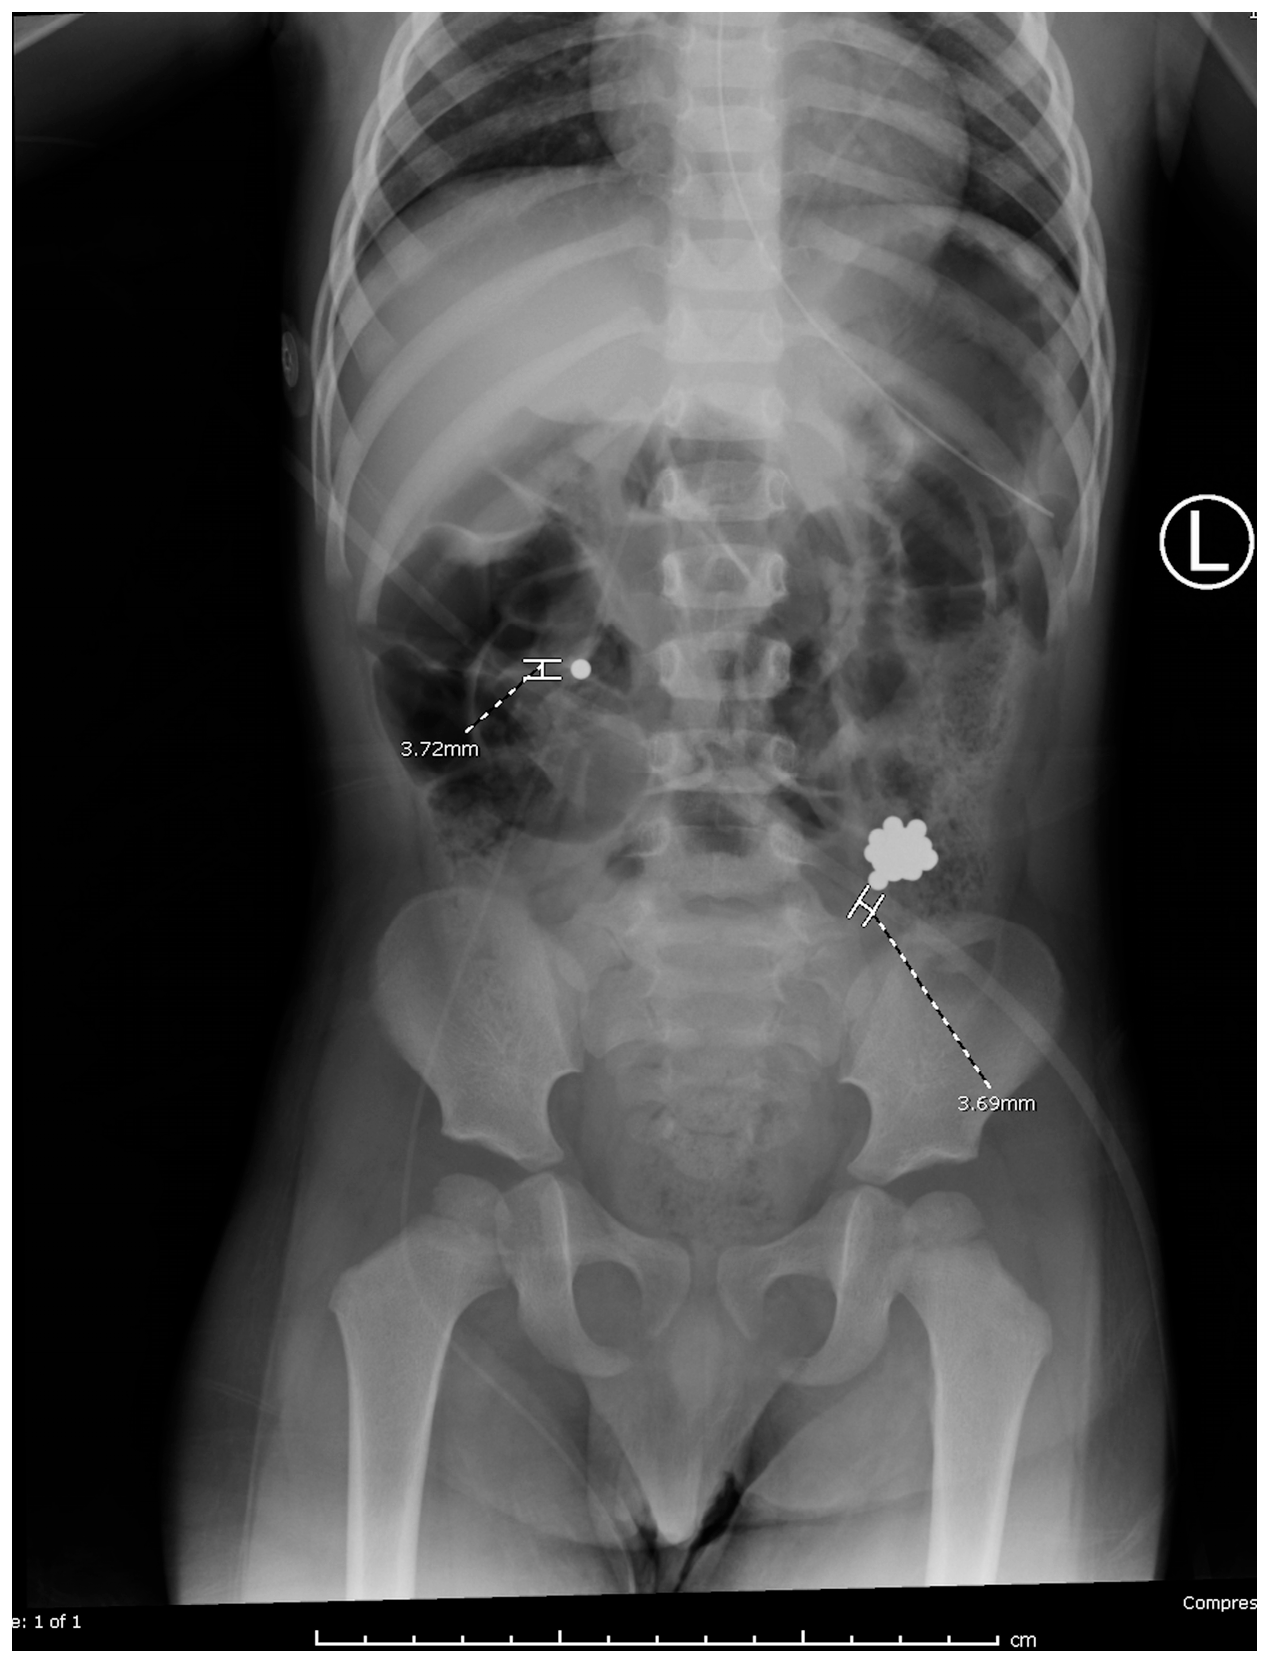

Plain radiographs demonstrated metallic densities clustered in the oropharynx, stomach, and small bowel (Figure 1). Recognizing the risks of gastrointestinal perforation and necrosis, the ED team initiated immediate multidisciplinary consultations with otolaryngology, gastroenterology, and general surgery. Magnet ingestions have been increasingly reported in pediatric literature due to their accessibility and the unique risks they pose to gastrointestinal tissues [4,5,6,7,8,9,10].

Figure 1. The radiograph from outside hospital reveals two magnets trapped in the oropharynx, with additional magnets overlying the distal stomach and proximal small bowel.